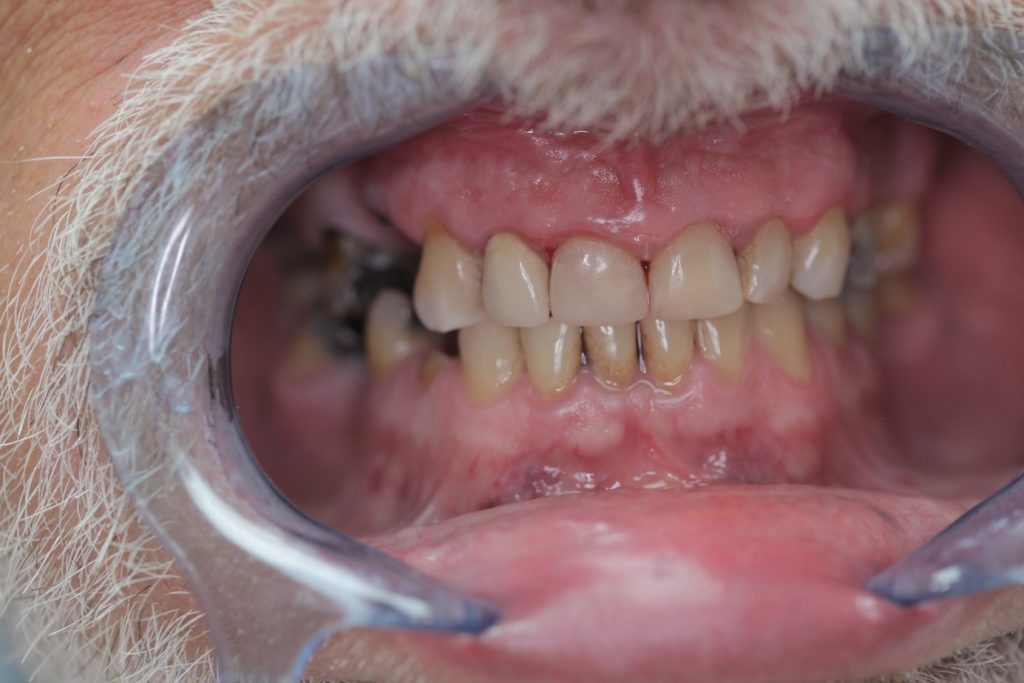

Multiple front teeth fillings, edge restorations using Asteria composite (Case presentation) (54)

A male patient, aged 67, reported to our clinic with the aim of having his condition assessed. He received a detailed treatment plan for his dental problems, which meant the fabrication of a full-arch bridge for his upper jaw. During the patient’s 2-day stint in Hungary we tried to focus on dealing with the most critical problems.

The front teeth were filled using Tokuyama Asteria Estelite filling materials.